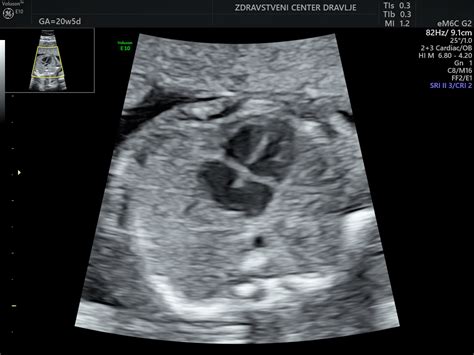

Tudi v 30. tednu se ocenjuje rast ploda z ultrazvočnimi meritvami, kot so prečni presek čez glavico (BIP), obseg glavice (HC), obseg trebuha (AC) in dolžina stegnenice (FL). Iz teh meritev se oceni telesna teža ploda.